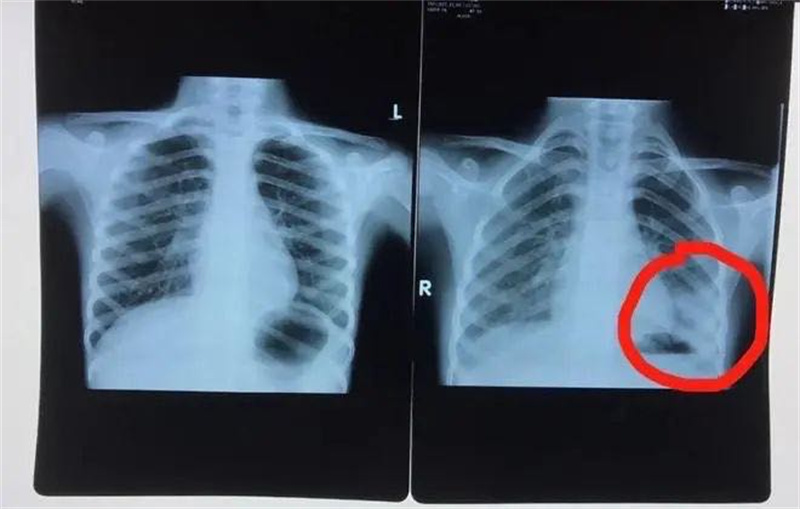

最近“大叶性肺炎”越来越多,宝爸、宝妈都慌了!原来是肺炎支原体肺炎来了!最近发热、咳嗽的宝宝越来越多,吃药、打针感觉效果都不好,来徐州市儿童医院呼吸科一检查,结果发现一侧或两侧肺叶变“白”了,病原体检测显示支原体感染阳性。这就是最近十分流行的肺炎支原体肺炎(MPP)。

肺炎支原体肺炎在我国大多数见于5岁以上儿童,是这个年龄段儿童最常发生的社区获得性肺炎。肺炎支原体感染肺部后可累及支气管、细支气管、肺泡以及肺间质。